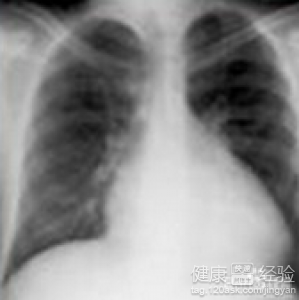

這個要看你的病情發展到什麼程度了,一般來說,只要是接受正規治療還是有希望治愈的。擴張型心肌病其實是一種左右心室擴張,或者是單心室擴張造成的疾病,而心髒衰竭則是擴張型心肌病的並發症之一,患者在得了這類疾病之後會出現呼吸困難,胸部疼痛,胸悶氣短,暫時性休克,昏迷,嚴重的還會出現死亡的後果,患者應該慎重的對待。